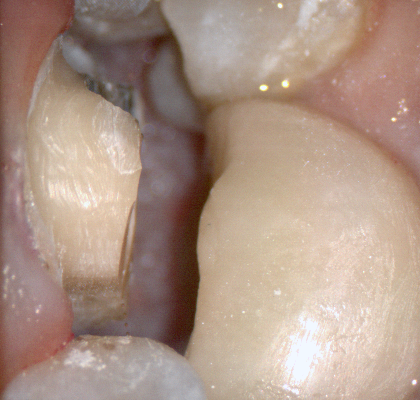

The following pictures depict the sequence of burs we recommend that you use to finish a preparation quickly. While patient is getting numb, take a quick look at the clearance you will need to reach proper material thickness. Once the quadrant is isolated with isolite and optragate, take an occlusal router bur and create a trough to gain the proper depth. Follow that with a flat disk, and you can quickly reduce the occlusal height.

A shoulder bur of .8 mm thickness can help you reduce the interproximal areas as well as the buccal and lingual margin lines. Before finishing the prep, place hemostatic agent like expasyl in the sulcus and place retraction cord. while it is setting, check your reduction. If you need more space, now is the time to reduce some more.